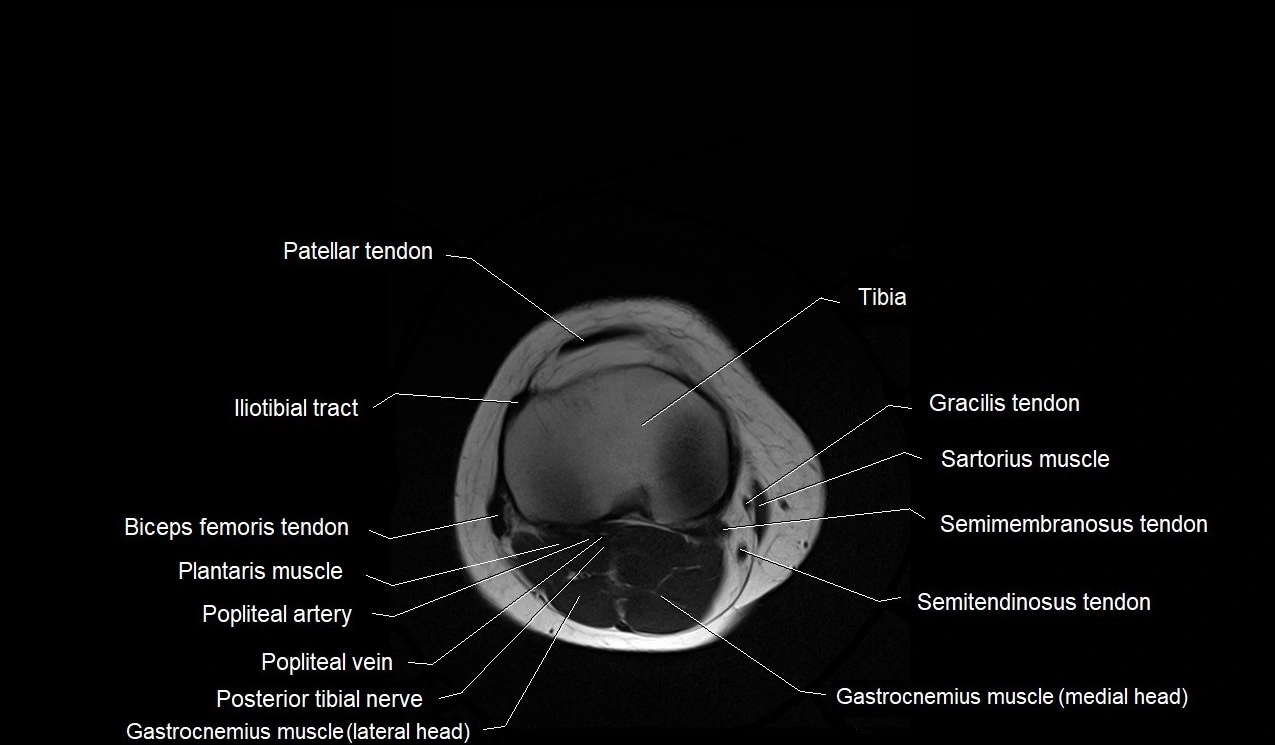

- Gastrocnemius muscle

- Gracilis tendon (Distal)

- Iliotibial tract

- Patellar tendon (patellar ligament)

- Plantaris muscle

- Popliteal artery

- Popliteal vein

- Sartorius muscle

- Semimembranosus muscle

- Semitendinosus muscle

- Tibia

- Tibial nerve